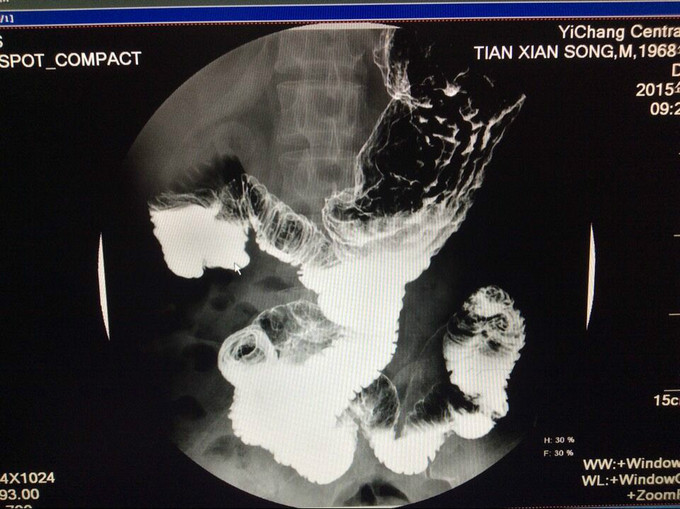

主诉:方向盘伤,胰头十二指肠破裂,肝十二指肠韧带撕裂伤术后8月,复杂肠漏1例。 2.现病史:患者因8月前因腹部外伤,当地医院行剖腹探查术,术中发现胆管、胰管、十二指肠损伤,肠系膜上静脉撕裂,行胰十二指肠切除,胰肠+胆肠+胃空肠Y吻合。术后出现重度感染休克、外伤性胰腺炎,予以腹腔引流术+空肠造瘘置营养管术,行抗休克、抗炎治疗,现术后8月腹腔引流管持续引流出胆汁及肠液,经引流管造影可见造影剂流入肠管,行上消化道造影未提示胃及肠管穿孔。

入院查血: Blood-Rt(五分类): 白细胞 6.97*10^9/L,红细胞 3.84*10^12/L,血红蛋白 122 g/L,红细胞压积 37.3 %,血沉 42 mm/h 查体:无特殊异常,腹腔引流管偶有黄褐色浑浊液体流出,量约50-80ml,腹软,无压痛、反跳痛,二便正常。 辅检:上腹部CT提示:胆肠吻合口一直径约2cm结石 辅助检查见上图

漏口位置,依据上消化道钡餐造影未见消化道穿孔,而从腹腔引流管处注入碘水造影可见肠管及隐约胃形显示,估计漏口位置为胰腺空肠及胆管吻合处肠管漏口, CT提示:胆道结石,尝试拔管后漏口无法愈合,再次予以腹腔引流置管。 我们分析漏口无法愈合的原因为胰液及胆汁对自身组织的消化,术中胆肠吻合口处放置T管,及胰腺空肠段放置引流管,引流肠液,目的为减轻消化液对漏口的影响,术后原漏口愈合,但出现新唇状漏,采用T管经皮下隧道引流 ,原皮肤漏口缝闭,同时加用负压吸引。 讨论2点: 1.该病人初次少量胆漏合并胆道结石时是否需要手术治疗? 2.再次出现唇状漏时,患者消化液外漏引起局部皮炎,皮肤伤口周围组织腐蚀严重,采用T管经皮下隧道引流,能否起到良好的治疗效果?